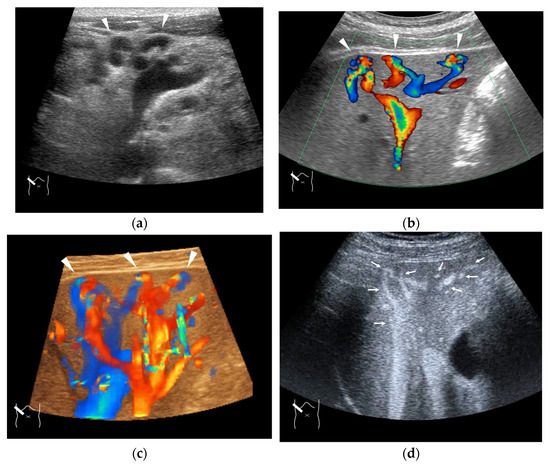

Currently, abdominal ultrasound is used in various ways, including contrast-enhanced elastography and endoscopic ultrasound, and is becoming a central part of the diagnosis of abdominal diseases. However, it is also true that there are still areas of abdominal diseases that have not been fully explored. It is necessary to focus on this area to advance the use of diagnostic ultrasound. For this reason, we are launching a Special Issue to collect related papers.

In this series, we will present cases with many lessons learned regarding liver, biliary, and pancreatic tumors, which are the main abdominal diseases, with a focus on external ultrasound and endoscopic ultrasound and will organize the information obtained to provide an objective and in-depth perspective on how to prevent misdiagnosis and draw conclusions that can be immediately applied to general clinical practice. To supplement this series, we will also include a detailed description of the peritoneum, mesentery, and omentum, which are always difficult to diagnose in daily clinical practice, as well as key points in the diagnosis of these pathologies.